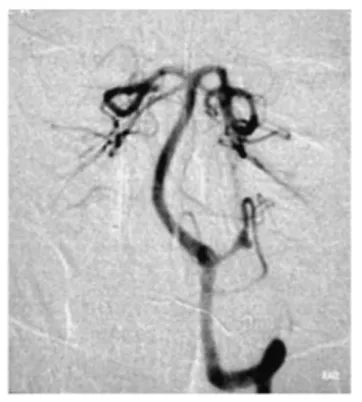

急诊头颅CT检查结果显示:第四脑室内出血。进一步行脑血管造影后发现,此次出血的"元凶"是位于左侧小脑后下动脉(PICA)的一枚动脉瘤。

结合患者的出血部位与动脉瘤特点,医生团队决定采用经髁入路实施动脉瘤夹闭手术。这一入路是颅底外科的经典术式,能够充分暴露小脑后下动脉及脑干侧方结构,同时手术创伤相对较小。

术后复查脑血管造影证实,动脉瘤已被成功夹闭,出血风险解除。术后病理报告亦表明,这枚偶然发现的肿瘤为Antoni A/B混合型神经鞘瘤。